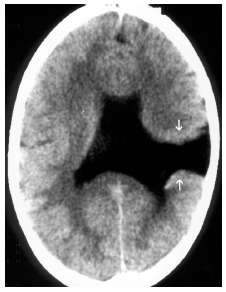

Considere que, após analisar a tomografia de um adulto jovem com crises epiléptica, foi notada uma alteração importante na imagem, como apresentado a seguir.

Enunciado 932438-1

Diante desse quadro neurorradiológico e da imagem apresentada, qual é o diagnóstico?